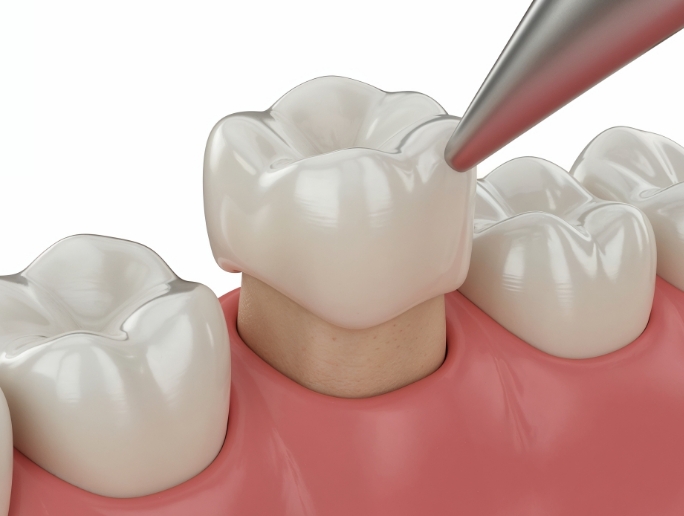

在进行根管治疗后, 为保护已变脆弱的牙齿,

通过整体包覆的方式进行修复,

是一种能同时恢复

受损牙齿功能的治疗,

并改善牙齿的美观效果